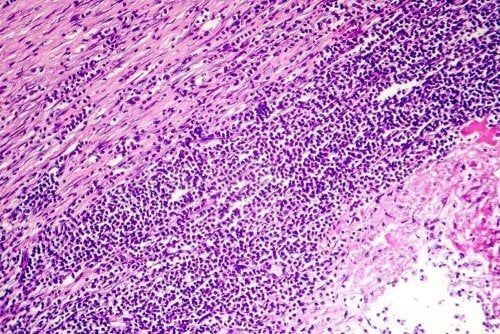

- Przewlekłe zapalenie osierdzia powstaje w wyniku pogrubienia osierdzia lub nagromadzenia sporych ilości płynu osierdziowego. Trwa ono ponad sześć tygodni i może prowadzić do niewydolności prawej komory serca. Powoduje także charakterystyczny obrzęk w okolicy brzucha, okolicy przedsionkowej i w kostkach.

Ponadto przewlekłe zapalenie osierdzia występuje wtedy, gdy włóknista tkanka tworzy się wokół serca, uciska je i zwiększa ciśnienie w żyłach, które przenoszą do niego krew. Tak więc płyn osierdziowy przestaje krążyć i gromadzi się w innych częściach ciała.